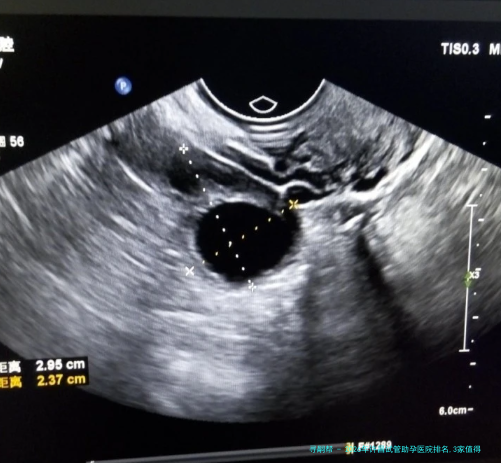

该机构的胚胎实验室配置了先进的胚胎培养系统,能够实施囊胚培养与移植等重要技术,有效提高胚胎着床率。实验室严密执行质量控制体系体例,保证胚胎培育和移植流程的安全程度与精确性。该机构还特别注重医生和患者沟通,为病患提供清晰的治疗方案解释和温馨的诊疗环境。